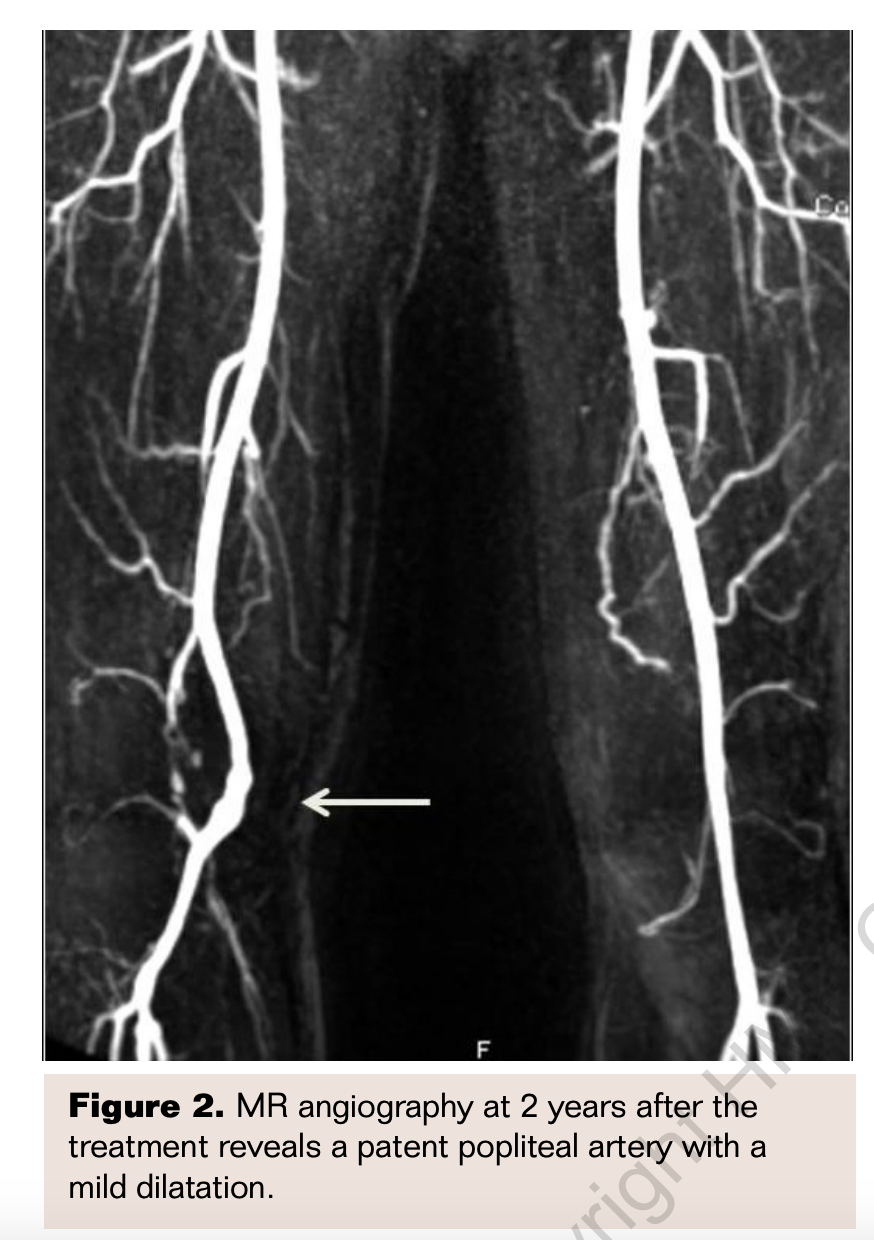

The surgical and endovascular outcomes were good and there were no intraoperative or postoperative complications. The patients had a median follow-up of 64 months (range, 41-100 months). Three of 5 patients had an uneventful, long-term follow-up and did not need any further intervention. Follow-up CDUS or MRA revealed patent popliteal arteries in these patients, but 1 patient had a small popliteal artery aneurysm visualized by MRA at 2 years (Figure 2). Two patients had recurrent thrombosis of the popliteal artery after treatment. One of these patients had repeated endovascular treatments at 4 and 18 months because of rethrombosis of the femoral and popliteal arteries. This oldest patient had the worst distal run-off (distal embolic occlusions of all crural arteries) and concomitant atherosclerotic stenosis of the distal femoral artery treated by stenting. After repeated endovascular treatments, he was asymptomatic. However he presented with a delayed thromboembolic occlusion in his follow-up, therefore below-knee amputation was performed in another institution 30 months after the first intervention. In another patient, recurrent thrombosis of the popliteal artery was observed 1 week after the decompressive surgery. This patient refused endovascular reintervention and underwent bypass surgery.